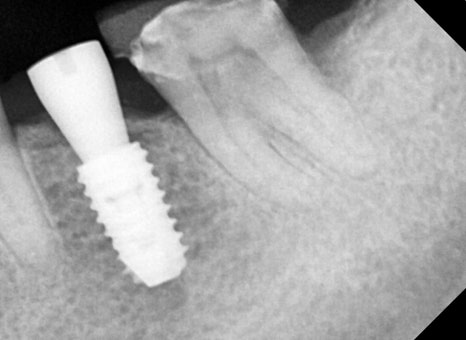

Right photo: Partial X-ray taken before root canal treatment after removing the existing crown (covered tooth).

➡ Deep decay had developed inside the old prosthesis, and root canal treatment was absolutely necessary.

➡ There was pain and discomfort, and along with root canal treatment, functional restoration was also performed with an implant in the missing front-tooth area.